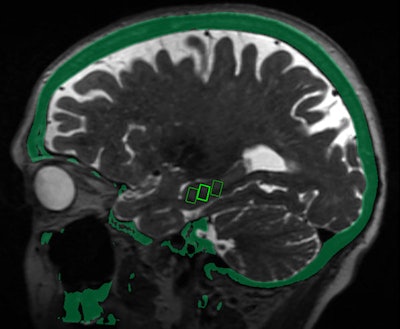

MRI brain scans performed immediately after MRgFUS revealed that the blood-brain barrier opened within the target areas of the brain and closed within 24 hours.

"We were able to open the blood-brain barrier in a very precise manner and document closure of the barrier within 24 hours," added study co-author Dr. Rashi Mehta, an associate professor at WVU. "The technique was reproduced successfully in the patients, with no adverse effects."